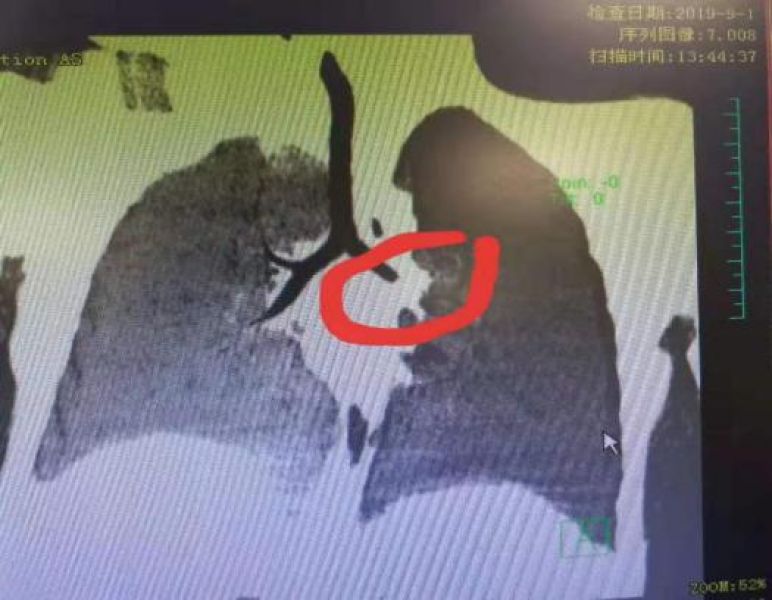

9月1日中午,又有一名2岁患儿因“进食枣子后咳嗽3天”入院。患儿3天前在家中哭吵时进食枣子,而后突然出现呛咳、喘息。完善胸部CT示左主支气管异物,值班医生田亮医师立即予氧气吸入,嘱咐家属不让患儿哭吵,并安抚患儿。他立即报告石敏主任、彭燕平护士长,联系宋小珍主治医师以及休息在家的刘翠主治医师和李毓英护士,急诊加班行经纤支镜支气管内异物取出术,历时20余分钟,一小粒新鲜红枣果肉被顺利取出,术后患儿咳嗽、喘息立即缓解,家长一颗悬着的心总算是放下了。